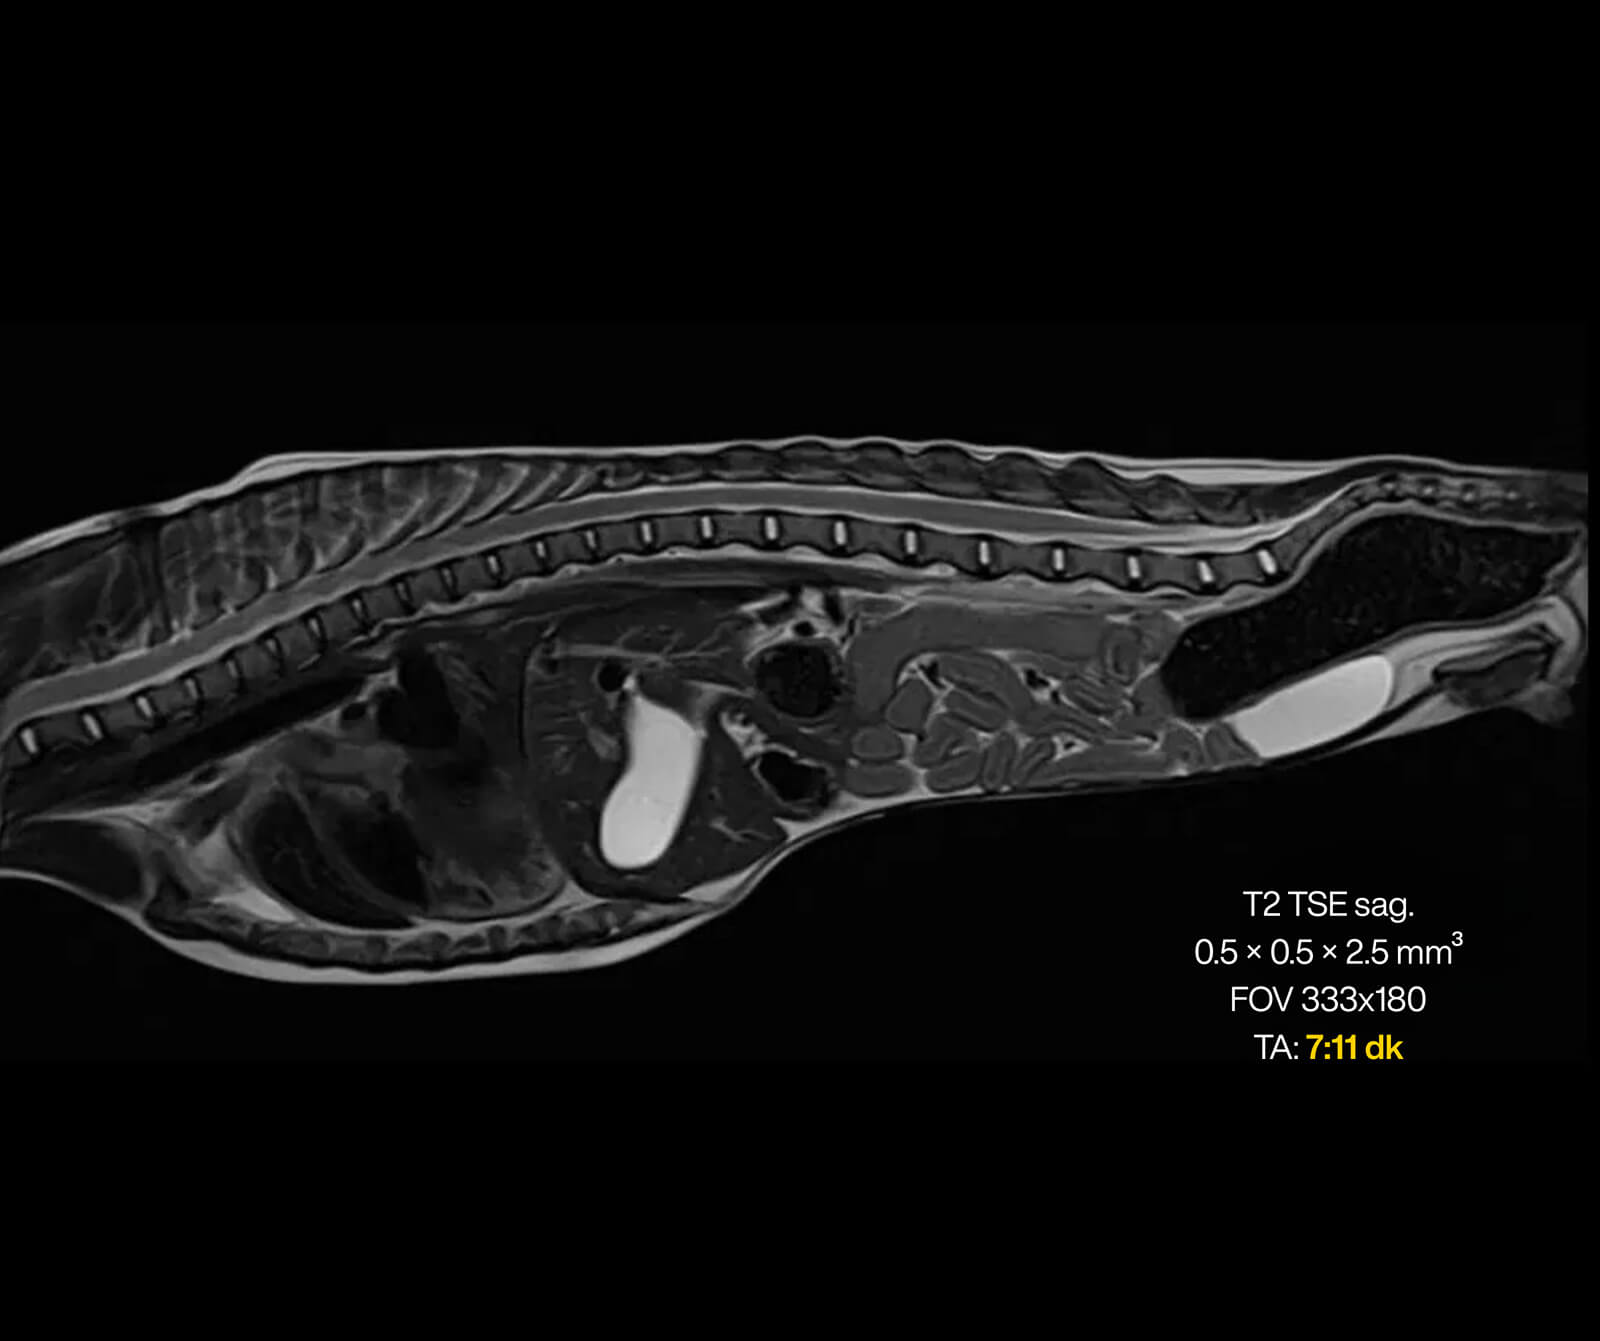

Veteriner hekimliğinde MR; beyin, omurilik, sinir sistemi, kas-iskelet sistemi ve iç organ hastalıklarının değerlendirilmesinde kritik rol oynar. Kemik yapılar dâhil olmak üzere vücudun tüm bölgeleri MR ile ayrıntılı şekilde incelenebilir.

• Omurga ve disk hastalıkları

• Spinal kord incelemeleri

• Disk hernisi, omurga tümörleri, enfeksiyonlar ve spinal stenoz

• Omurilikte travmatik ve dejeneratif değişiklikler